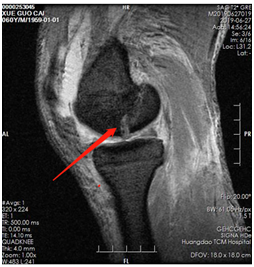

薛大叔左膝外侧有(以腓骨小头为中心)约10cmX15cm皮肤挫伤,其中间约5cmX8cm皮肤色紫,血运差;膝关节内上侧有约6cmX25cm皮肤挫伤,血运不满意 。医生为其进行了详细检查,确诊为左股骨内后髁骨折(Hoffa骨折)、左腓骨小头骨折、左膝内侧半月板损伤、左下肢挫裂伤 。

术前磁共振片